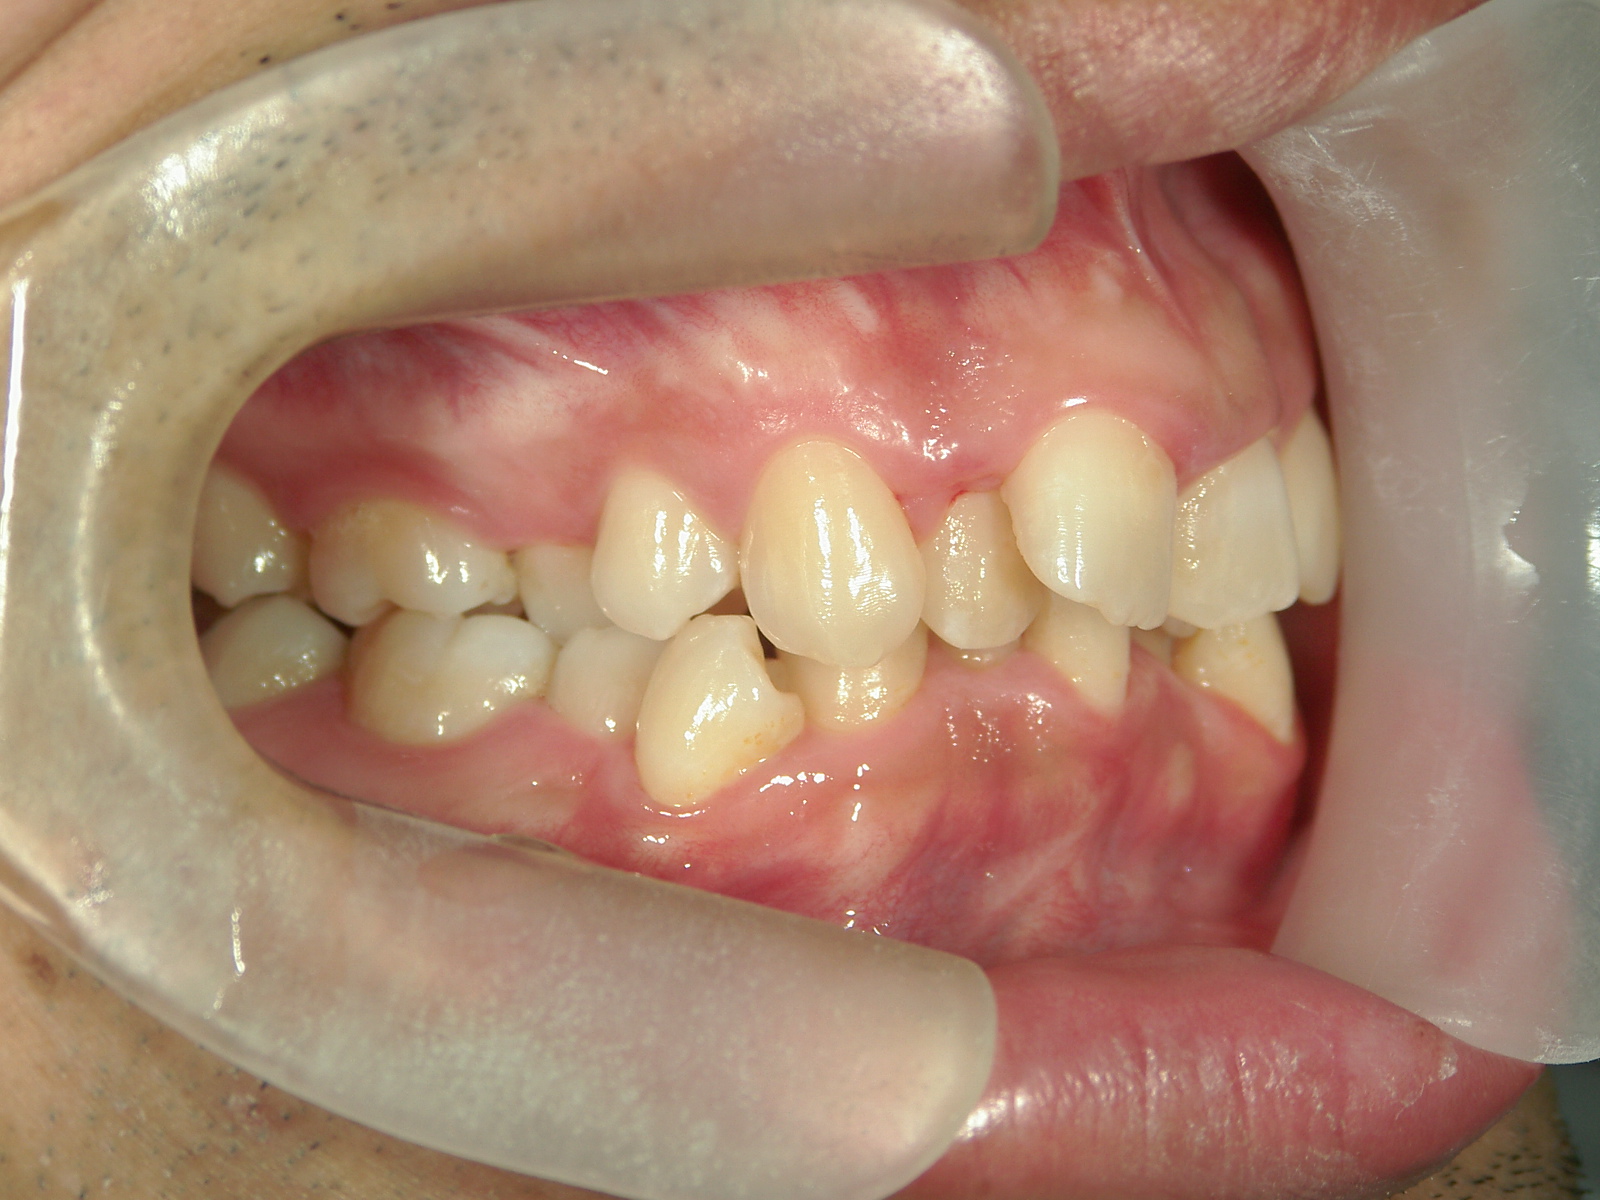

全顎ワイヤー矯正 症例(79)

主訴: 前歯が噛み合わない。歯並びが気になる。

上下左右 第一小臼歯(4本)、上下右 親不知(2本)抜歯。

ミニインプラント、アップライトスプリングを併用。

カテゴリー : ガタガタ(叢生) , 噛み合わせが深い(過蓋咬合)